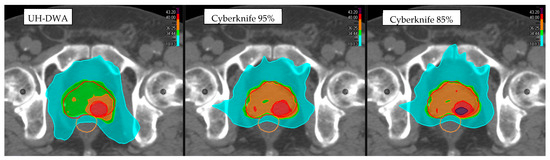

3. Results

3.1. Target Coverage

3.2. Organs at Risk